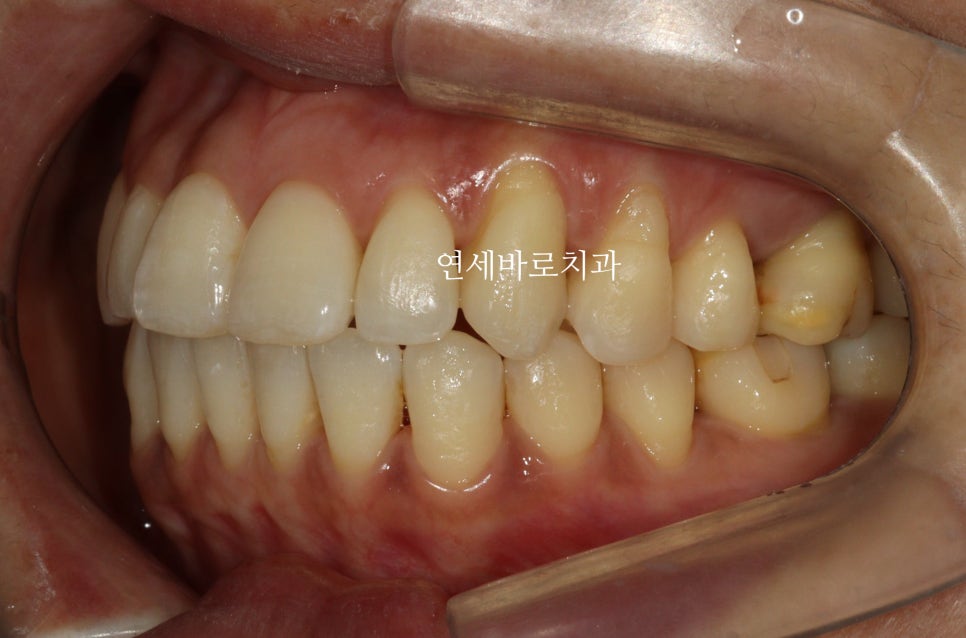

2023년 9월 16일: 치료 시작

9/16에 장치를 착용하기 시작하셨고,

사진입니다.

부족한 부분을 맞추기 위해 응급처치등을 처리하였고